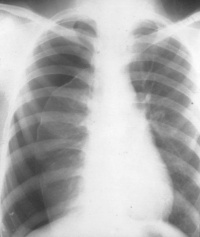

X线胸片检查是诊断气胸的重要方法,可显示肺受压程度,肺内病变情况以及有无胸膜粘连、胸腔积液及纵隔移位等。气胸的典型X线表现为外凸弧形的细线条形阴影,称为气胸线,线外透亮度增高,无肺纹理,线内为压缩的肺组织。大量气胸时,肺脏向肺门回缩,呈圆球形阴影。大量气胸或张力性气胸常显示纵隔及心脏移向健侧。合并纵隔气肿在纵隔旁和心缘旁可见透光带。

肺结核或肺部慢性炎症使胸膜多处粘连,发生气胸时,多呈局限性包裹,有时气胸互相通连。气胸若延及下部胸腔,肋膈角变锐利。合并胸腔积液时,显示气液平面,透视下变动体位可见液面亦随之移动。局限性气胸在后前位胸片易遗漏,侧位胸片可协助诊断,或在x线透视下转动体位可发现气胸。

气胸容量的大小可依据x线胸片判断。由于气胸容量近似肺直径立方与单侧胸腔直径立方的比率[(单侧胸腔直径。一肺直径。)/单侧胸腔直径。)],侧胸壁至肺边缘的距离为1cm时,约占单侧胸腔容量的25%左右,2cm时约50%。故从侧胸壁与肺边缘的距离≥2cm为大量气胸,<2cm为小量气胸。如从肺尖气胸线至胸腔顶部估计气胸大小,距离≥3cm为大量气胸,<3cm为小量气胸。

(一)X线胸部检查:为最可靠诊断方法,可判断气胸程度、肺被压缩情况、有无纵隔气肿、胸腔积液等并发症